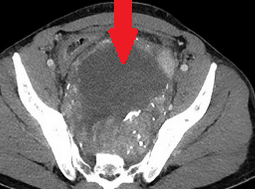

Surgical specimen. Complete resection of the tumor together with a segment of rectum (Courtesy Dr. V. Penopoulos)